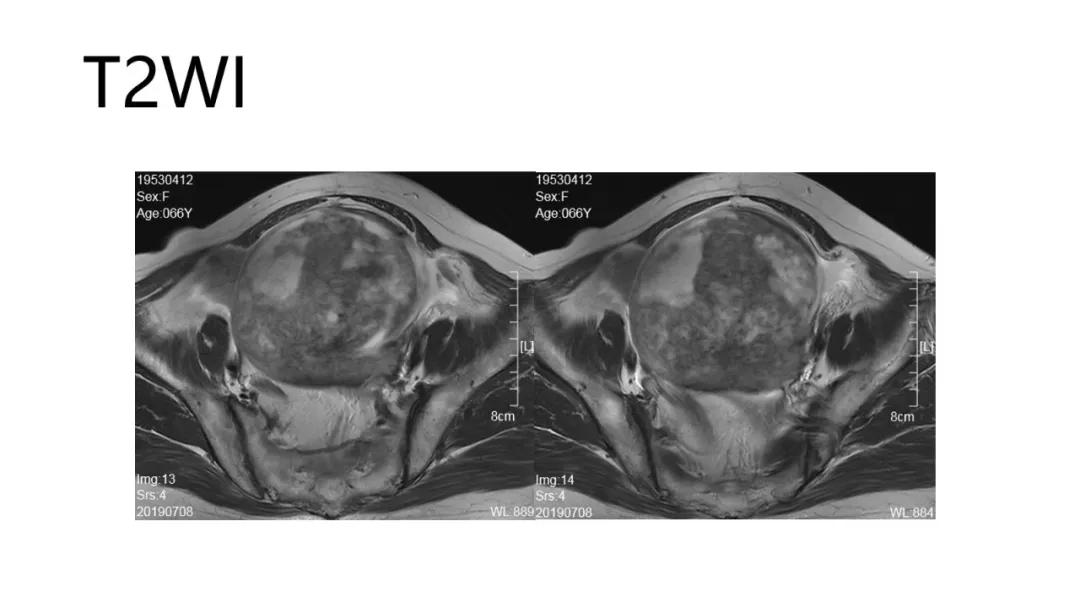

病理:颗粒细胞瘤

病理:子宫肌瘤粘液样变性